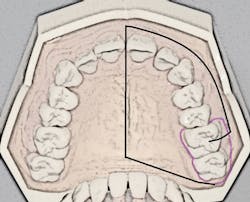

The porous palatal tissue and bone allow penetration of the anesthetic to the dental plexus of the ASA and MSA nerves (on one side), which provide innervation to pulps of the premolars through incisors and, sometimes, the mesiobuccal root of the first permanent molar. The same-side hard palate and palatal gingiva are also anesthesized (see Figure 1).

Recall that the posterior superior alveolar (PSA) nerve block, with its 95% success rate, anesthetizes the molar teeth and associated buccal soft tissues. The ability to anesthetize an entire maxillary quadrant (hemimaxilla) during NSPT with the AMSA and the user-friendly PSA block combination (see Figure 1) results in a reduction of the total number of injections (two versus four to five) and also a reduction of total volume of anesthetic (1.25 to two cartridges versus two to three cartridges). Patients appreciate the reduced number of penetrations as well as the lack of numbness of the lip and face.